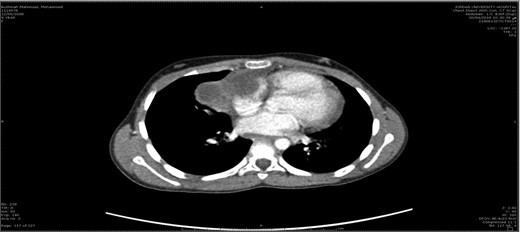

A 10-year-old female patient was well prior to an evaluation for chest pain of two weeks duration, at which an anterior mediastinal mass, was noted on chest radiograph. Chest X-ray (Fig. 1) showed a well-defined homogenous opacity in the right upper and mid zones extending from mediastinum and obliterating the hilar shadow. Transthoracic echocardiography revealed a pericardial effusion. Chest CT (Fig. 2) revealed a well-defined tumor mass involving the anterior mediastinum adjacent to the heart measuring 6 × 4 cm. Mild amount of pericardial fluid noted.